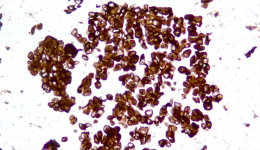

| Description | CLDN18.2是Claudin蛋白質(zhì)家族的一員,位于細胞膜表面,Claudin18.2(CLDN18.2)表達具有特異性。其作為Claudins蛋白的一個(gè)亞型,在正常組織中僅表達于分化的胃黏膜上皮細胞。在胃癌、食管癌和胰腺癌等多種腫瘤中表達,并且不僅限于原發(fā)病灶,在轉移灶中也有表達。目前臨床研究中使用的檢測方法均為免疫組化。 |

| 切片厚度 | 4μm |

| 示例 | ![]() |

| IHC染色結果 | |